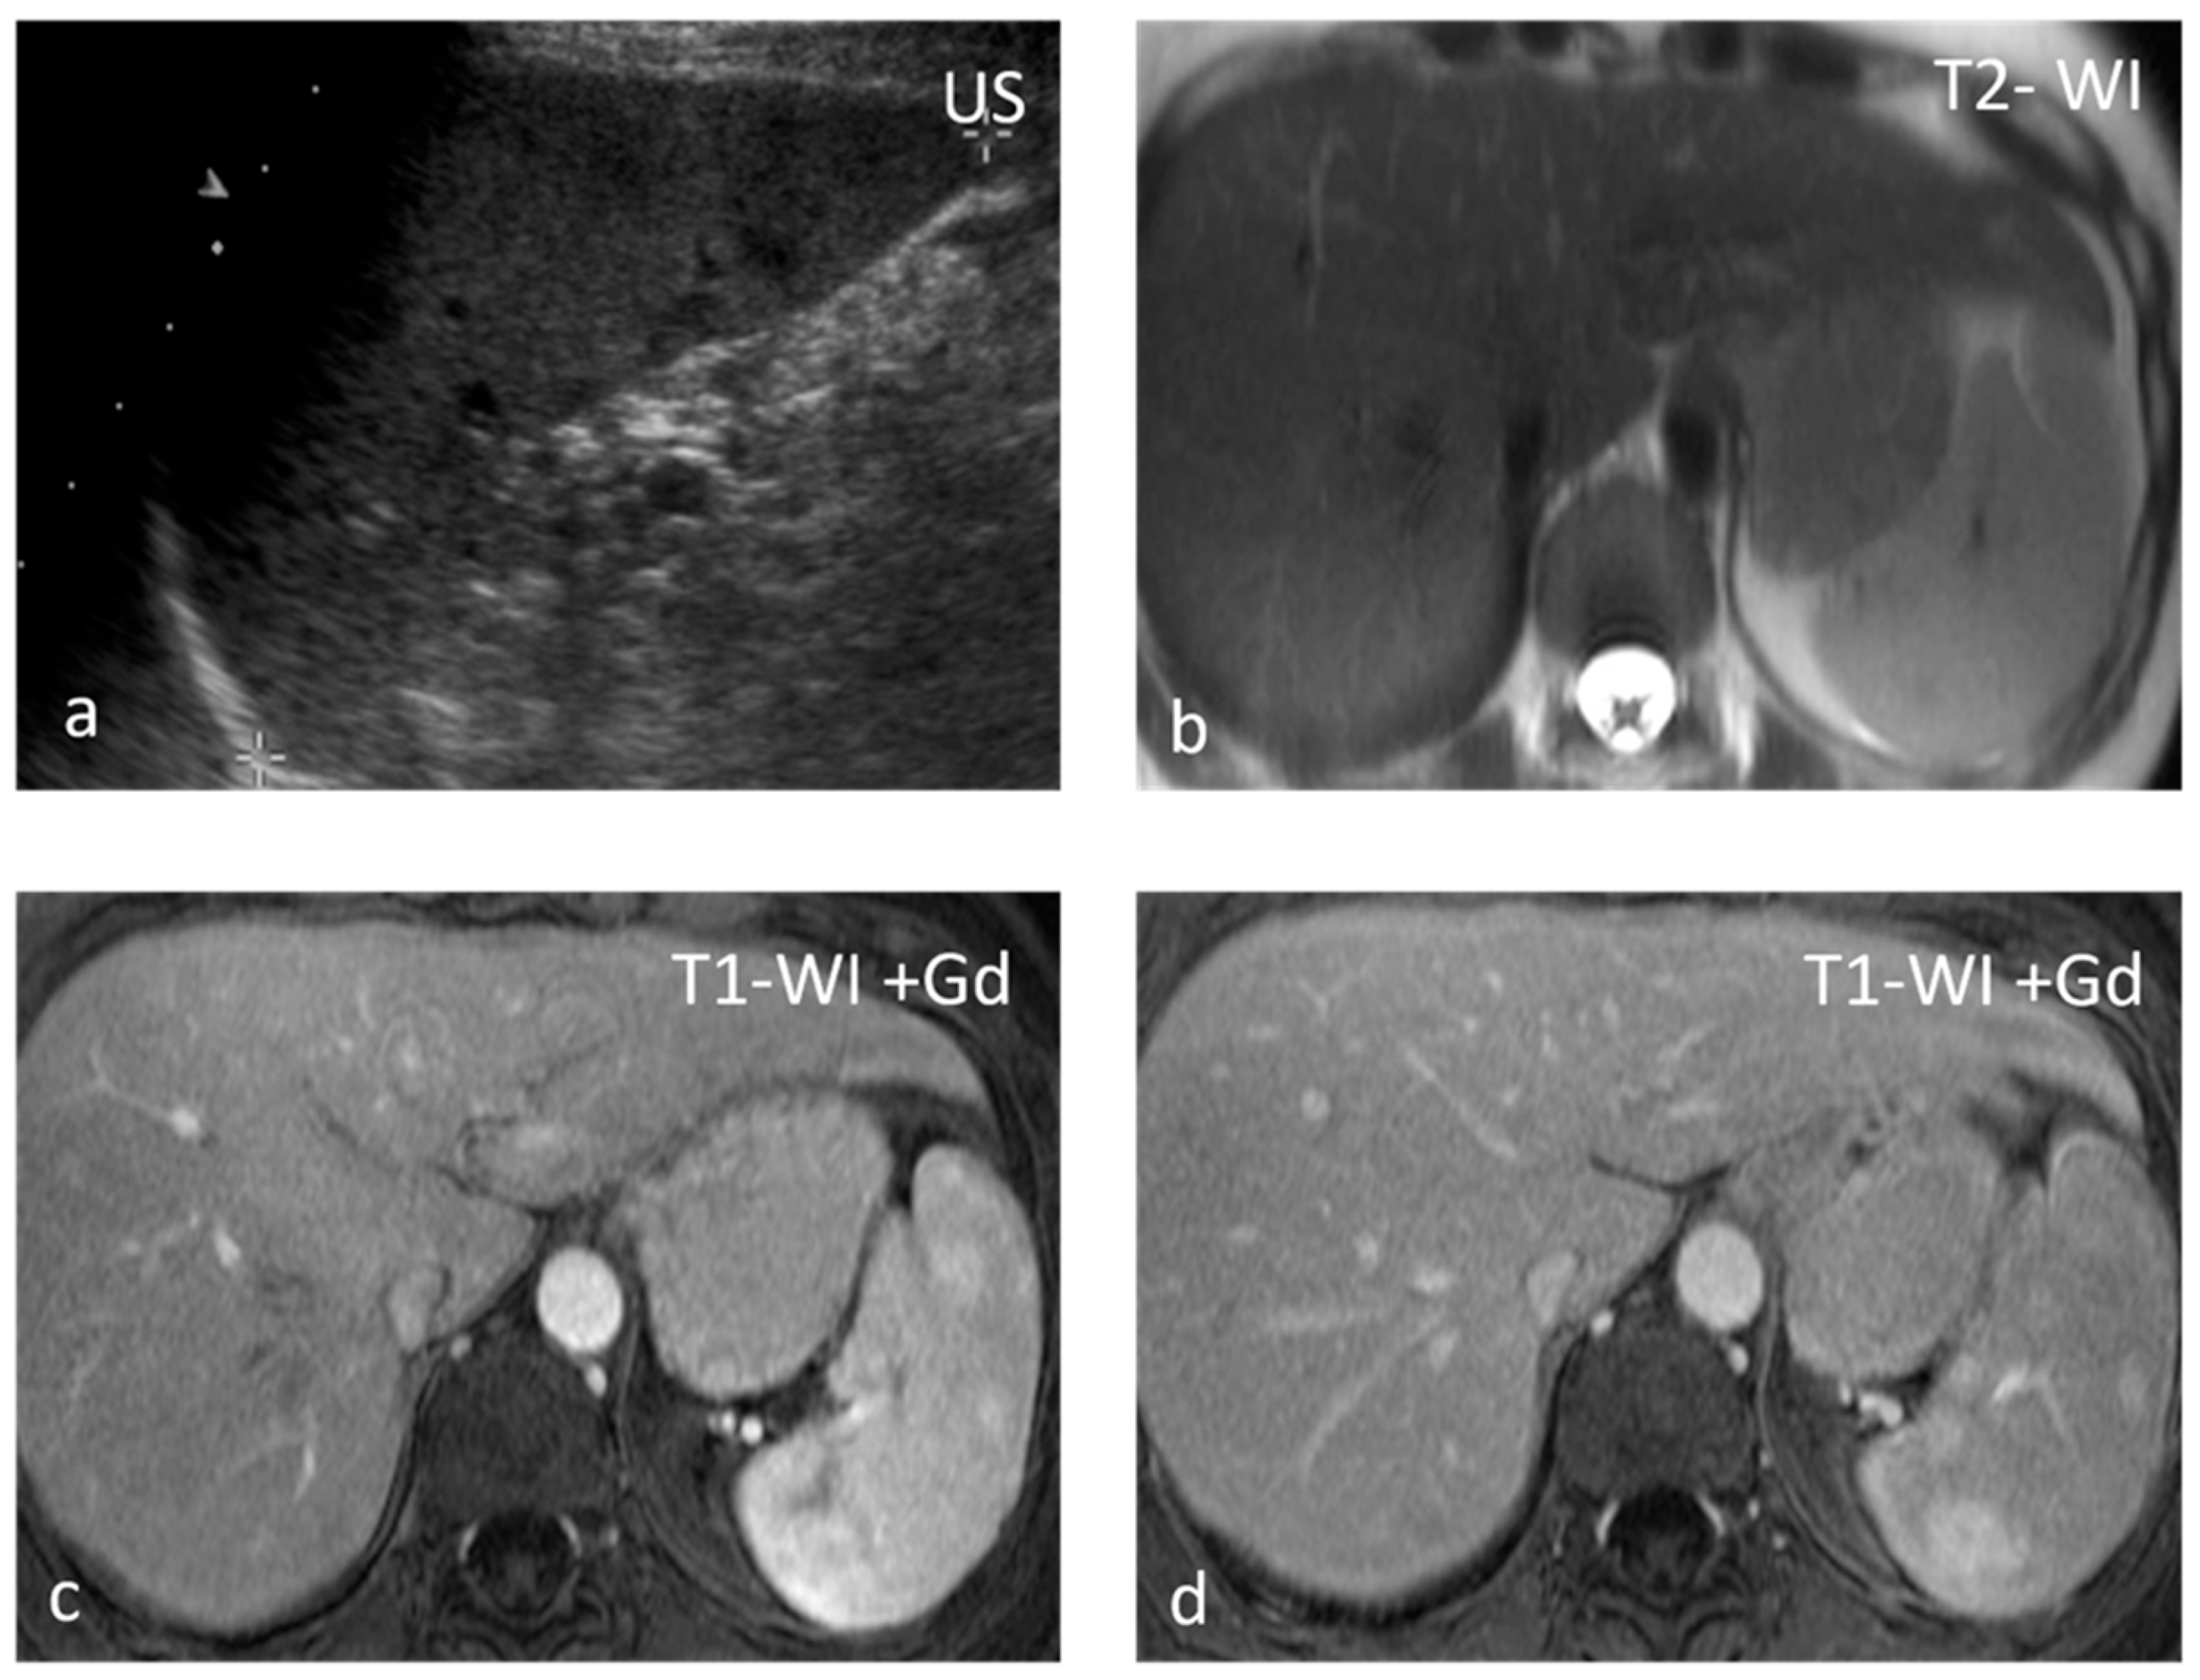

Sarcoidosis is a multisystem disease characterized by the presence of non-caseating granulomas. One-third of patients presenting with splenic sarcoidosis findings have normal chest radiography [18]. Splenic involvement has been reported in about 40% of cases of multisystem sarcoidosis, but isolated sarcoidosis of the spleen is extremely rare [19]. It may present either as splenomegaly or with multiple nodules, whereas a solitary splenic lesion is very rare. Patients with diffuse splenic granulomas have a worse prognosis in terms of persistent chronic sarcoidosis than patients without splenic involvement or patients with limited splenic disease [20]. Nodules appear hypodense on CT and have low SI both on T1-WI and T2-WI, with minimal delayed enhancement [21] (Figure 2). Nodules are best seen on T2-WI with fat saturation and on early gadolinium-enhanced T1–WI. MRI is said to be able to monitor disease activity, as during active inflammation, nodules demonstrate T2-WI hyperintensity due to edema and high vascular permeability, as well as restricted diffusion [22]. The main differential diagnosis includes infections, especially tuberculosis, and malignancies, especially lymphoma. The final diagnosis is based on three main criteria: a compatible presentation, the evidence of non-caseating granulomas on histological examination, and the exclusion of any alternative diagnosis [23].

Figure 2.

Sarcoidosis. US shows multiple hypoechoic nodules (a). The nodules appear slightly hypointense on T2 WI (b) and show mild delayed enhancement (c,d).